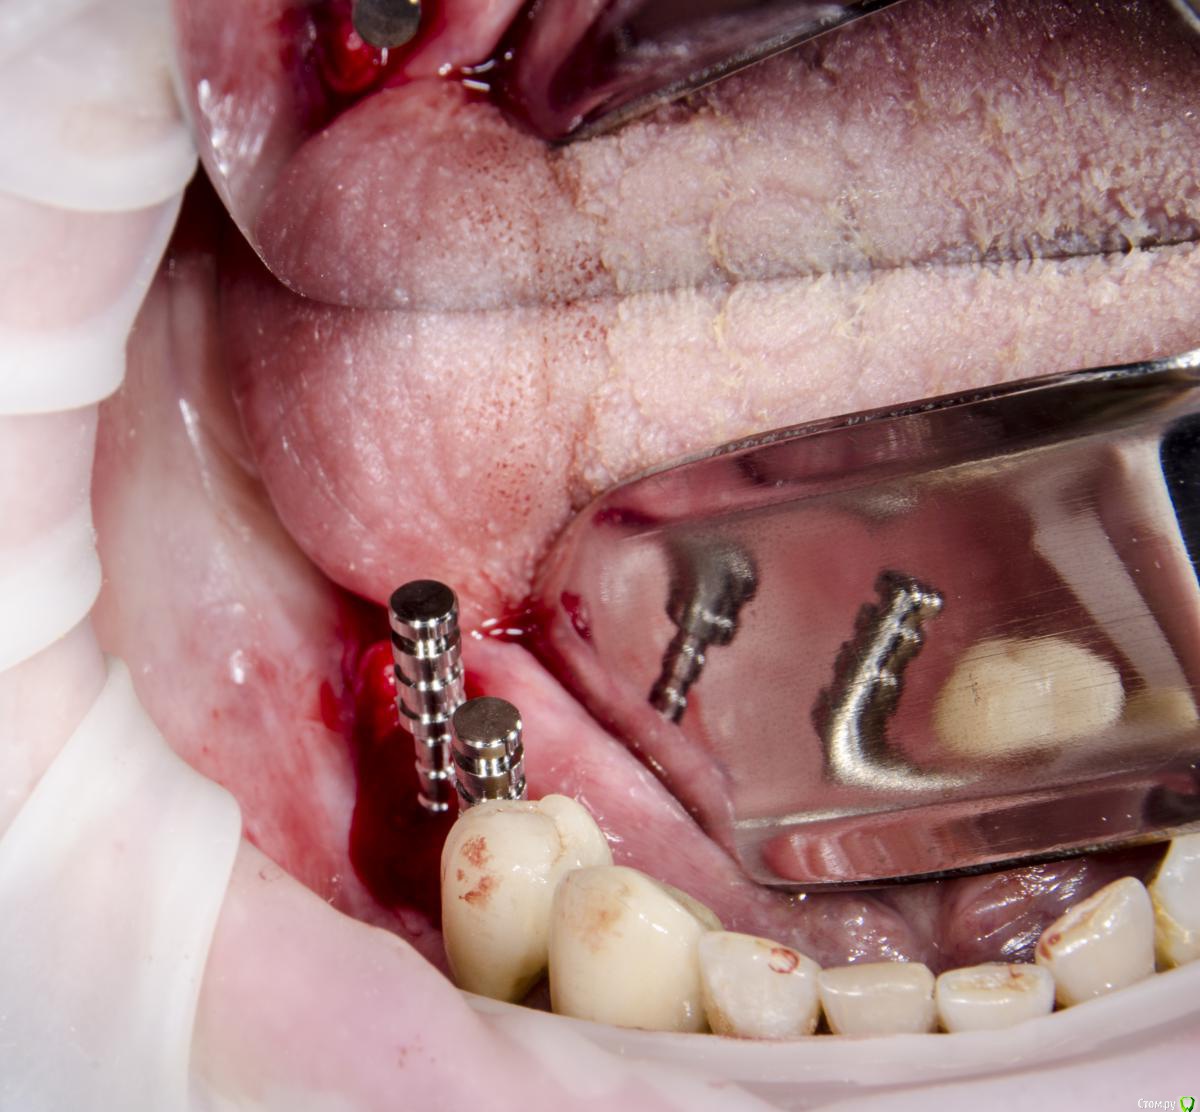

kamranchick Опубликовано 12 сентября, 2015 Поделиться Опубликовано 12 сентября, 2015 Доброго всем дня и хороших выходных)вопрос следующего планаПациент обратился с жалобами на отсутствие зубов пациент среднего достатка.начали потихоньку работать, сверху все зубы удалили, начали имплантирование снизув области 4 сегмента установили 2 имплантата в области 45 46, так как условия неплохие, в области 7 зуба начинается скос, ну и придется либо заваливать имплантат язычно либо делать пластику, как Вы думаетестоит ли вкручивать имплантат в область 7 зуба?тогда наверное и с другой стороны придется вкручивать, так как там отсутствует 4567зуб, ну а сверху как вы поняли зубов нету уже, ни одного)кт если кому то понадобятся. срезу кину в в в будние дни) Ссылка на комментарий

Magomed Опубликовано 13 сентября, 2015 Поделиться Опубликовано 13 сентября, 2015 завалите язычно, для чего придумали угловые абатменты. Ссылка на комментарий